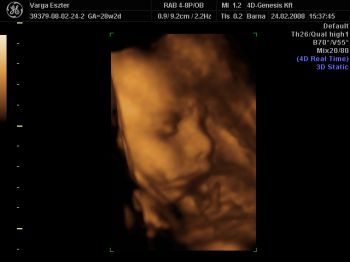

Tegnap voltunk a 4dgenesisben. Természetesen összecsomagolta magát, az arcáról csak pár felvételt tudott készíteni a nő, pedig 1 órán át próbálkozott, hátha kimozdul ebből a pozícióból. Mondta, hogy meglökögeti, nem fog fájni, de a férjem nem engedte. Azt mondta, nem baj, majd amikor megszületik meglátjuk milyen. Azért pár jó fotót sikerült készíteni. Megpróbálom felrakni. Nagyon kedves volt a nő, tényleg mindent megpróbált a lökögetésen kívül. Még csokit is kaptam, meg üdítőt, hátha arra megmozdul. A babával minden rendben, 1400g. A méhlepény 0 fokban érett.

Emma - Nagyon édes a Babó :) Látom, alvó üzemmódban kaptátok el ti is ;) akkor olyan kis nyugodt, kiegyensúlyozott, kisimult a pofijuk a képeken :) Nagyon szép GYerkőc ;)

Igen a kezei. Az egyik könyökét végig az arca előtt tartotta, legtöbbször a térde és a könyöke összeért. Szinte összecsomagolta magát. Volt, hogy a talpát a fejére tette. Ja, és azt mondták,hogy elég sok haja van. Még két képet felrakok. Kép Kép Emma

Köszönöm a dicsérteket! Természetesen, mint minden anyuka, nagyon elfogult vagyok. Állandóan nézegetem, hogy milyen aranyos. Találgatjuk, melyik testvérére hasonlít. Mindenki mást lát benne.

Hihetetlen, hogy milyen pózokat képesek felvenni odabenn. :D A mi picurunk kb. 30 percig le sem vette a lábát a fejecskéjéről. Csak a végén tudtuk elkapni a pofiját egy-két percre. :D